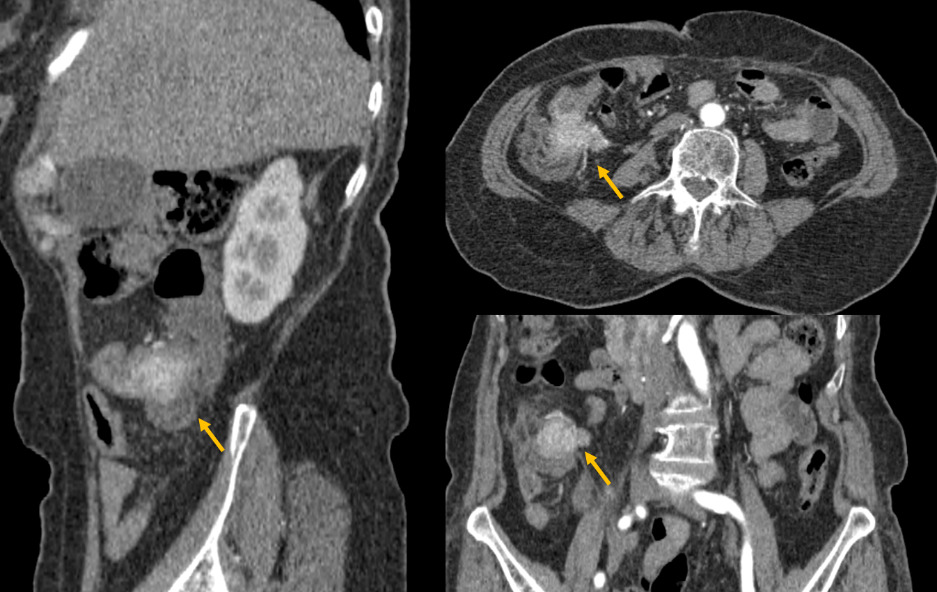

Therefore, he underwent a triple phase abdominal CT scan, revealing a poorly defined tumoral lesion in the ileocecal region, with irregular borders infiltrating the proximal colon and adjacent fat (Figure 1). The lesion showed early and intense enhancement in the arterial phase, suggesting hypervascularity. Additionally, CT-scan confirmed a well-circumscribed hypodense lesion in segment VI of the liver, which also showed early arterial enhancement (Figure 2).

Due to the nature of the enhancement, the diagnosis of a neuroendocrine colonic tumor with liver metastasis was considered. A biopsy confirmed a diagnosis of poorly differentiated neuroendocrine carcinoma of the right colon. Given the high histological grade, the patient’s general condition, and the presence of hepatic metastasis, primary surgical management was not considered appropriate, and chemotherapy was proposed. Unfortunately, the patient passed away before starting treatment.